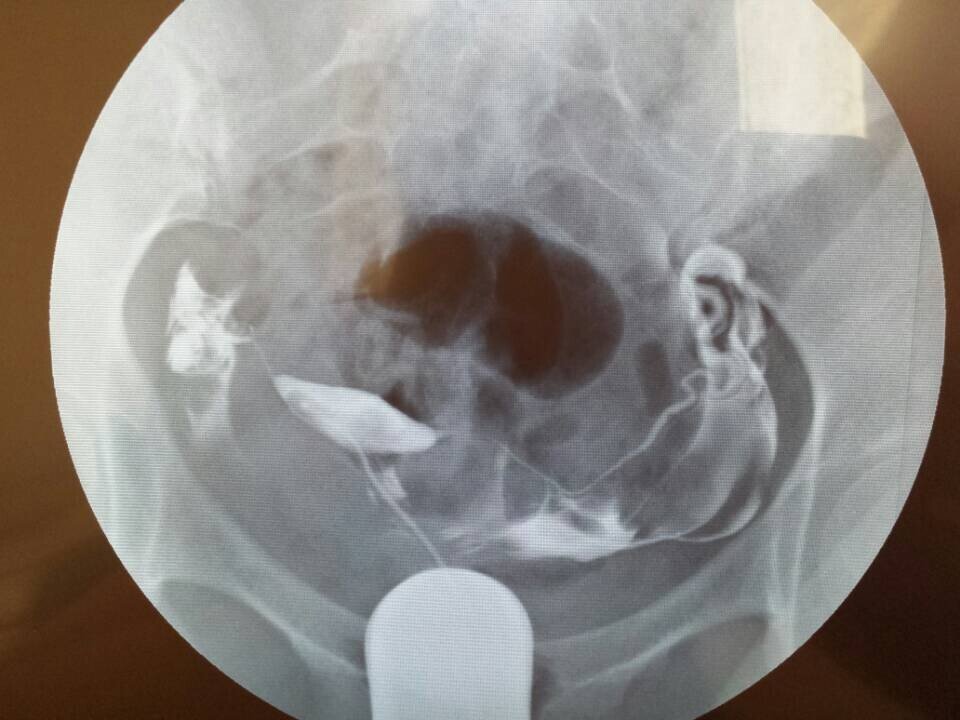

求医生帮我看一下输卵管造影的片子,在当地的妇婴医院造影后,医生太忙,没有给仔细讲解,希望专家帮我看下该采用什么方案,是否严重,如何治疗,跪谢!~有慢性阑尾炎病史,月经周期一直不准,40-50天左右来一次月经,雌激素比较低,一直在喝中药调理月经。备孕6个月监测排卵但是一直没有怀孕,这个月初做了碘油输卵管造影,当时患者太多,大夫没有做过多讲解,就给开了两盒治疗盆腔炎的药,也没有告诉用不用挂吊瓶消炎,现在造影后一个星期了,右侧输卵管部位每天都会隐隐的疼,是否该需要输液呢?